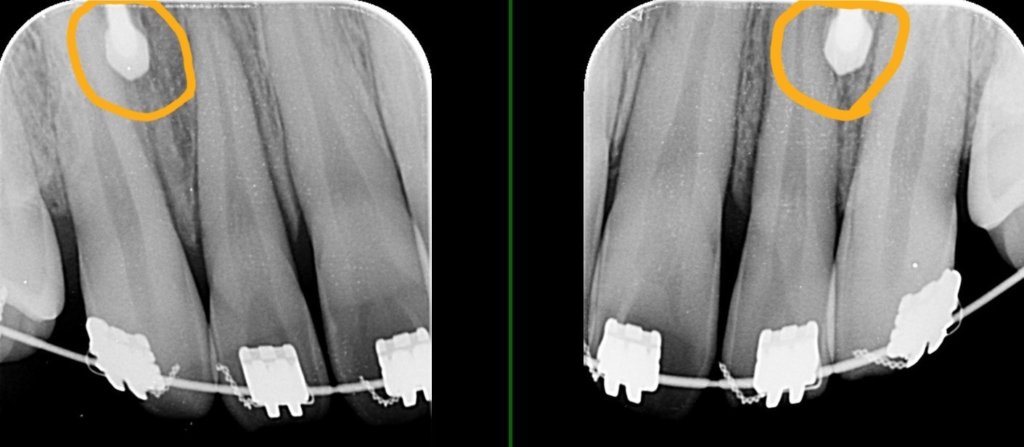

レントゲン写真を確認すると、

この患者さんの場合、

*歯並びの写真で見ると「出っ歯」であるとは分かり難いですが、頭部全体のレントゲン写真を見ると、出っ歯であることがハッキリと分かります。

レントゲン写真で確認すると、